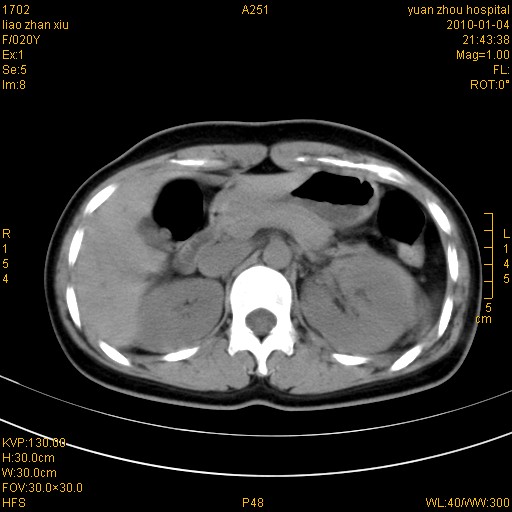

标题: CT23985:F20Y 外伤典型病例

左肾挫伤,包膜下积血。

左肾挫裂伤伴肾被膜下积血!另:肾周筋膜增厚!

1)左肾包膜下血肿。2)左侧肾挫伤可能;建议:行ct增强扫描检查。3)腰椎左侧横突骨折。

左肾挫伤,包膜下积血,l3、4左侧横突多发骨折。

双侧肾胞膜下出血,左侧较多。l3、4左侧横突多发骨折。

1、左肾挫伤,包膜下积血;

2、l3、4左侧横突多发骨折;

3、腹腔积气,考虑肠管破裂?

左肾挫伤,包膜下积血,L1、2、3、4左侧横突多发骨折。